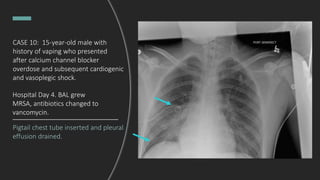

CASE 10: 15-year-old male with

history of vaping who presented

after calcium channel blocker

overdose and subsequent

cardiogenic and vasoplegic shock,

intubated and admitted to

pediatric ICU.

Hospital Day 4.

Pigtail chest tube inserted and pleural

effusion drained.

Hospital Day 4. BAL grew

MRSA, antibiotics changed to

vancomycin.